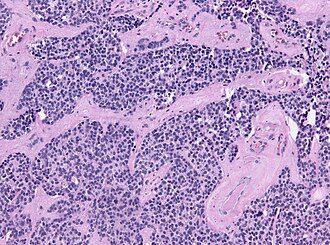

Microscopic

Features:[1]

- Small round (blue) cell tumour with:

- Stippled chromatin.

- High NC ratio.

- +/-Flexner-Wintersteiner rosette - rosette with empty centre (donut hole).

- +/-Fibrillary, eosinophilic material (neuropil-like).[2]

Images: